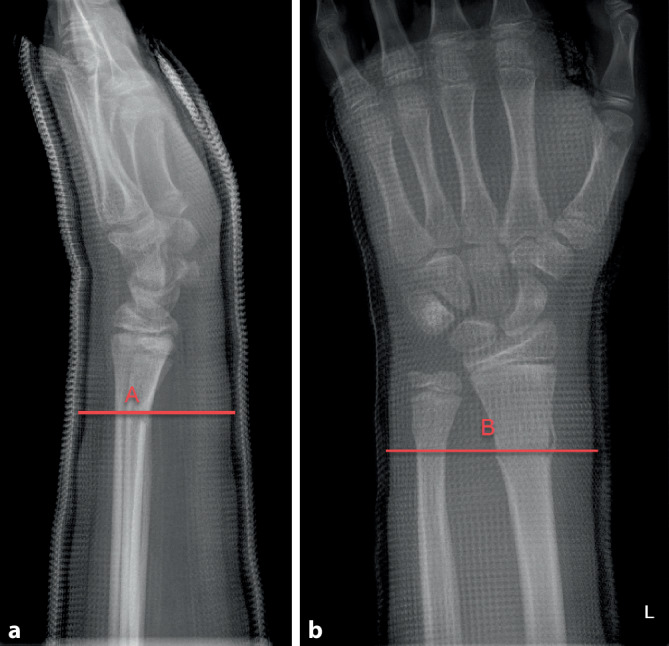

Damit ein Gips eine Fraktur zu halten vermag, muss er korrekt anmodelliert werden. Hierzu sollte das Wattepolster gleichmäßig verteilt sein und der Gips eng anliegen, ohne jedoch Druckstellen zu erzeugen. Das Anmodellieren des Gipses mit der flachen Hand, insbesondere im Frakturbereich, ist essenziell, erfordert jedoch etwas Übung und Erfahrung. Der Cast-Index ist ein Messwert, welcher zur Beurteilung des korrekten Anmodellierens herangezogen werden kann. Bestimmung des Cast-Indexes. Messung des Innendurchmessers (A) des Gipses auf Frakturhöhe im Seitenbild (a) geteilt durch den Innendurchmesser (B) des Gipses auf Frakturhöhe im a.-p. Bild (b). Optimal ist der Index bei 0,8 oder kleiner. Beachten Sie auch die durchgehende, gleichmäßige, aber nicht zu dick auftragende Polsterung

Der Cast-Index ist definiert als der innere Durchmesser des Gipses auf Frakturhöhe im Seitenbild geteilt durch den inneren Durchmesser des Gipses auf Frakturhöhe im a.-p. Bild (s. Abb. 6 und 7). Er ist ein Messwert zur Kontrolle des korrekten Anmodellieren des Gipses [4] Ein Cast-Index unter 0,80 gilt als guter prognostischer Faktor mit geringerem Risiko der sekundären Dislokation bei Vorderarmfrakturen [3, 4]. Die Datenlage zum Cast-Index ist zwar bis heute sehr dünn und heterogen, mehrere Studien konnten jedoch den positiven Effekt für den Cast-Index nachweisen [2]. Damit kann dieser Parameter zur Beurteilung eines „guten Gipses“ im Alltag unserer Meinung nach durchaus hilfreich sein.